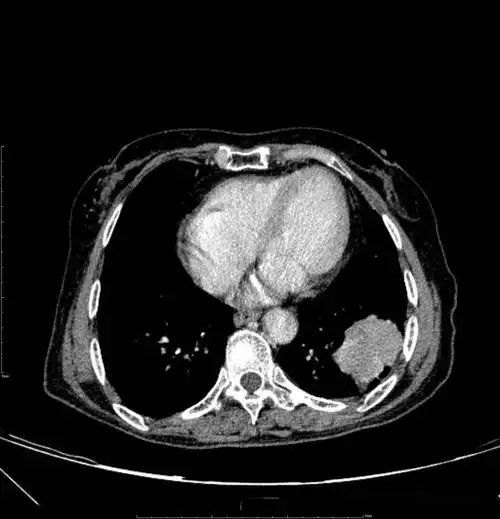

图片是患者ct平扫和多期增强扫描(动脉期,静脉期,平衡期或延迟期)的